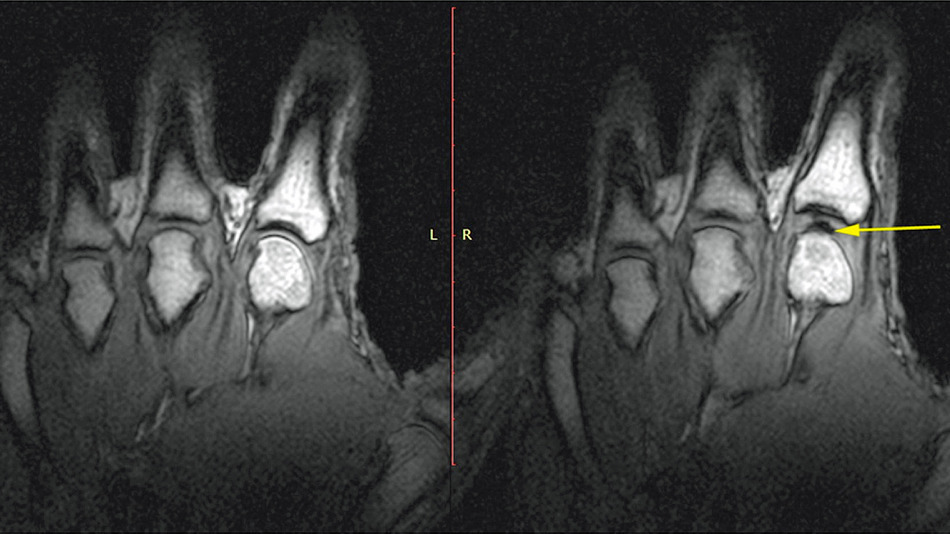

Probablemente en alguna ocasión hayas crujido tus dedos. Pues bien, los científicos no pudieron determinar en los últimos años por qué se produce ese sonido característico, pero hace algunos días un grupo de investigadores aseguró haber descubierto el origen de ese peculiar ruido, gracias a diversos experimentos con resonancias magnéticas. Según los expertos, lo que causa el crujido en nuestras manos es la creación de cavidades de gas en el líquido sinovial que tenemos entre los huesos. El crujido sucede en menos de 310 milisegundos. Los investigadores también detectaron que inmediatamente antes del chasquido se crea dentro de nuestras manos un flash blanco, aparentemente causado por el roce del mencionado líquido. El estudio fue realizado en Canadá, dirigido por Greg Kawchuk, un profesor de medicina de rehabilitación en la Universidad de Alberta, y que ha sido publicado en la revista especializada PLOS ONE.